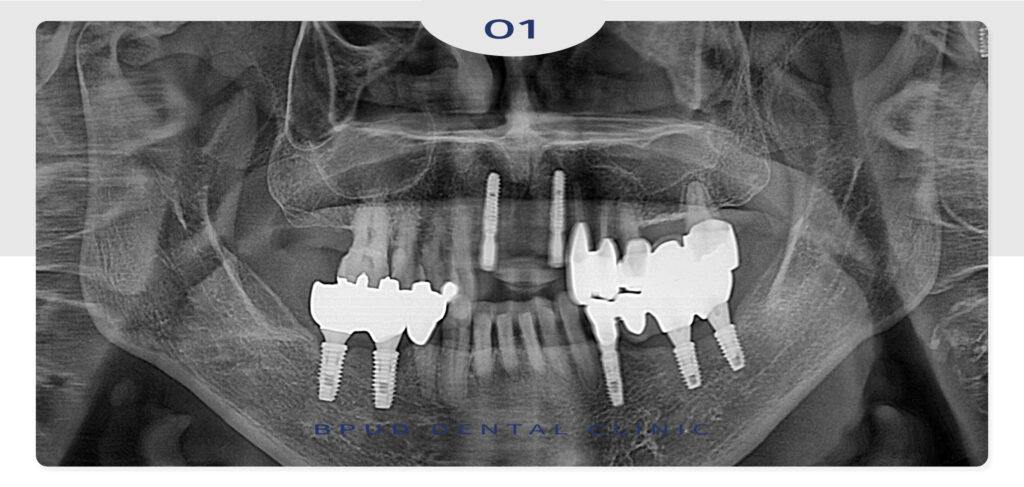

약 3개월 간의 기간동안 잇몸뼈와 임플란트가

충분히 융합될 수 있도록 기다려 주었습니다.

앞니 부위의 특성 상 조금만 잘못되어도

완성도가 떨어지고 부자연스럽게 보일 수 있어

숙련된 부평유디치과의 의료진과 충분히 논의한 후

시술해야 합니다.

3D 디지털 기기로 구강 내부를 면밀히 살피고

식립 부위의 특징을 꼼꼼히 확인한 후 인공치근을

정교하게 식립해야 합니다.